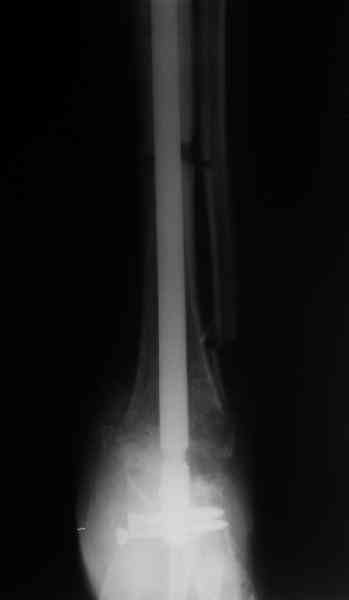

Приветствую, Павел и коллеги, ПИ> удлинения большеберцовой кости для компенсации укорочения поврежденной конечности. ПИ> В итоге: мы планируем выполнить пациенту большеберцово-пяточный ПИ> артродез в аппарате Илизарова с одновременной остеотомией берцовых В продолжение обсуждения, которое было 3 недели назад. Аналогичня операция одному нашему пациенту была сделана в конце февраля 2006. Дистракцию закончили 15 марта. На недавнем снимке нижний регенерат еще довольно хлипкий (снимок 1),

и мы не смогли обещать, что аппарат можно будет совсем скоро снять. Пациент выразил горячее желание расстаться с наружным фиксатором, даже если нужна еще одна операция. На этой неделе выполнили закрытое штифтование (впервые именно в такой ситуации) и сняли аппарат.